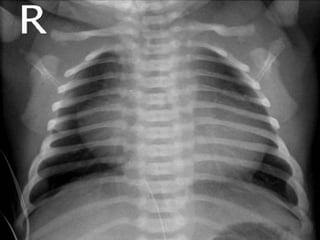

X-ray Studies

The heart size is normal or slightly increased, with

enlargement of the RA and LV. Pulmonary vascularity

decreases in most patients although it may increase in

infants with TGA.

Occasionally, the concave PA segment may produce a

boot-shaped heart, like the x-ray findings of TOF.

ELECTROCARDIOGRAPHY 1. “Superior” QRSaxis (between 0 and –90 degrees) is characteristic. It appears in most patients without TGA and in only 50% of patients with TGA. 2. LVH is usually present; RAH or biatrial hypertrophy (BAH) is common X-ray Studies The heart size is normal or slightly increased, with enlargement of the RA and LV. Pulmonary vascularity decreases in most patients although it may increase in infants with TGA. Occasionally, the concave PA segment may produce a boot-shaped heart, like the x-ray findings of TOF.